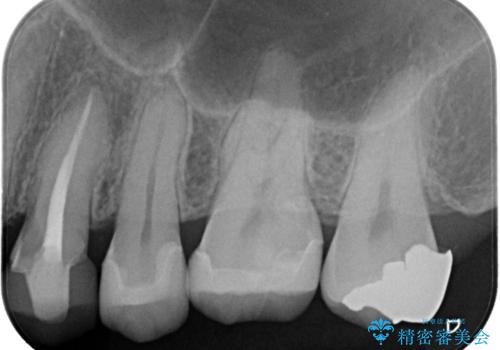

- 定期健診にて虫歯が見つかった患者さんです。他院で保険治療(CR、プラスチック)したところとまだ処置されていないところが虫歯になっていました。

セラミックインレーで治療しました。

以前保険治療で治したところが再び虫歯になっていました。保険治療で使用される材料は主にプラスチックなので必ず劣化がおきます。再治療のリスクを減らすために、セラッミックインレーで治療を行いました。セラミックインレーには劣化がほとんどありません。当院ではシリコンで型取りを行っているので、適合が良い被せものが出来き再治療のリスクを減らすことが出来ます。